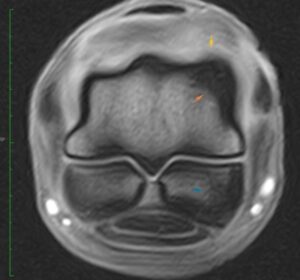

Signs: Bone edema or bone bruising are painful, so your horse will be sore. Your vet can isolate the painful area with nerve blocks, but sophisticated imaging techniques may be necessary to identify the cause. X-rays will not show microscopic bone damage, but a edema/hematoma may appear as a “hot spot” on a nuclear bone scan. MRI is a good diagnostic technology to outline the edema/hematoma.

MRI-Bone Edema